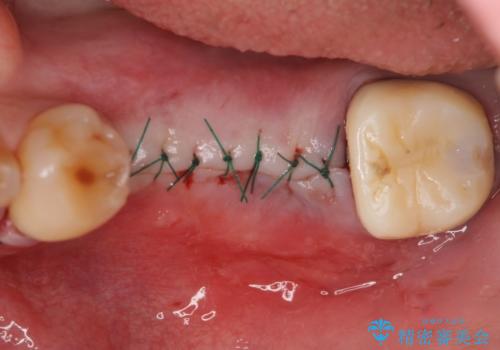

- 左下奥歯が虫歯で抜歯になってしまったため、インプラントにしたいといらっしゃった方の症例です。

欠損部位である左下5、6番目にインプラントを埋入し、オールセラミッククラウンによる補綴を行いました。

- 外科手術のため、術後に痛みや腫れ、違和感を伴います